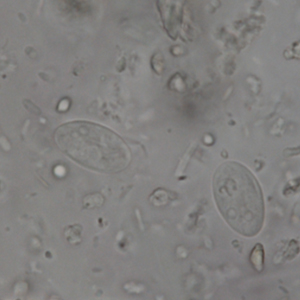

Giardia intestinalis cysts are oval, stain with Lugol and measure between 8 and 12 µm long. They have a thin outer membrane and contain two to four nuclei and many flagella (Strait et al., 2012).